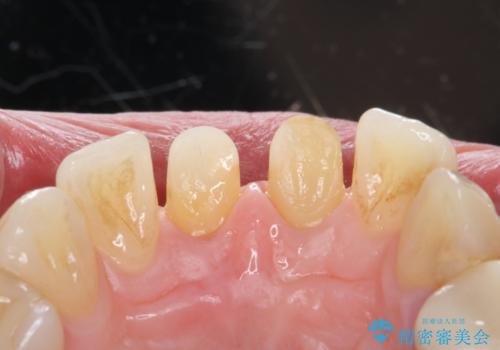

- 前歯の変色を主訴に来院されました。

変色に対してはかぶせ物で周囲の歯との色調を合わせます。

根管治療についてご説明をし、右上の1本だけ再根管治療を行うこととなりました。